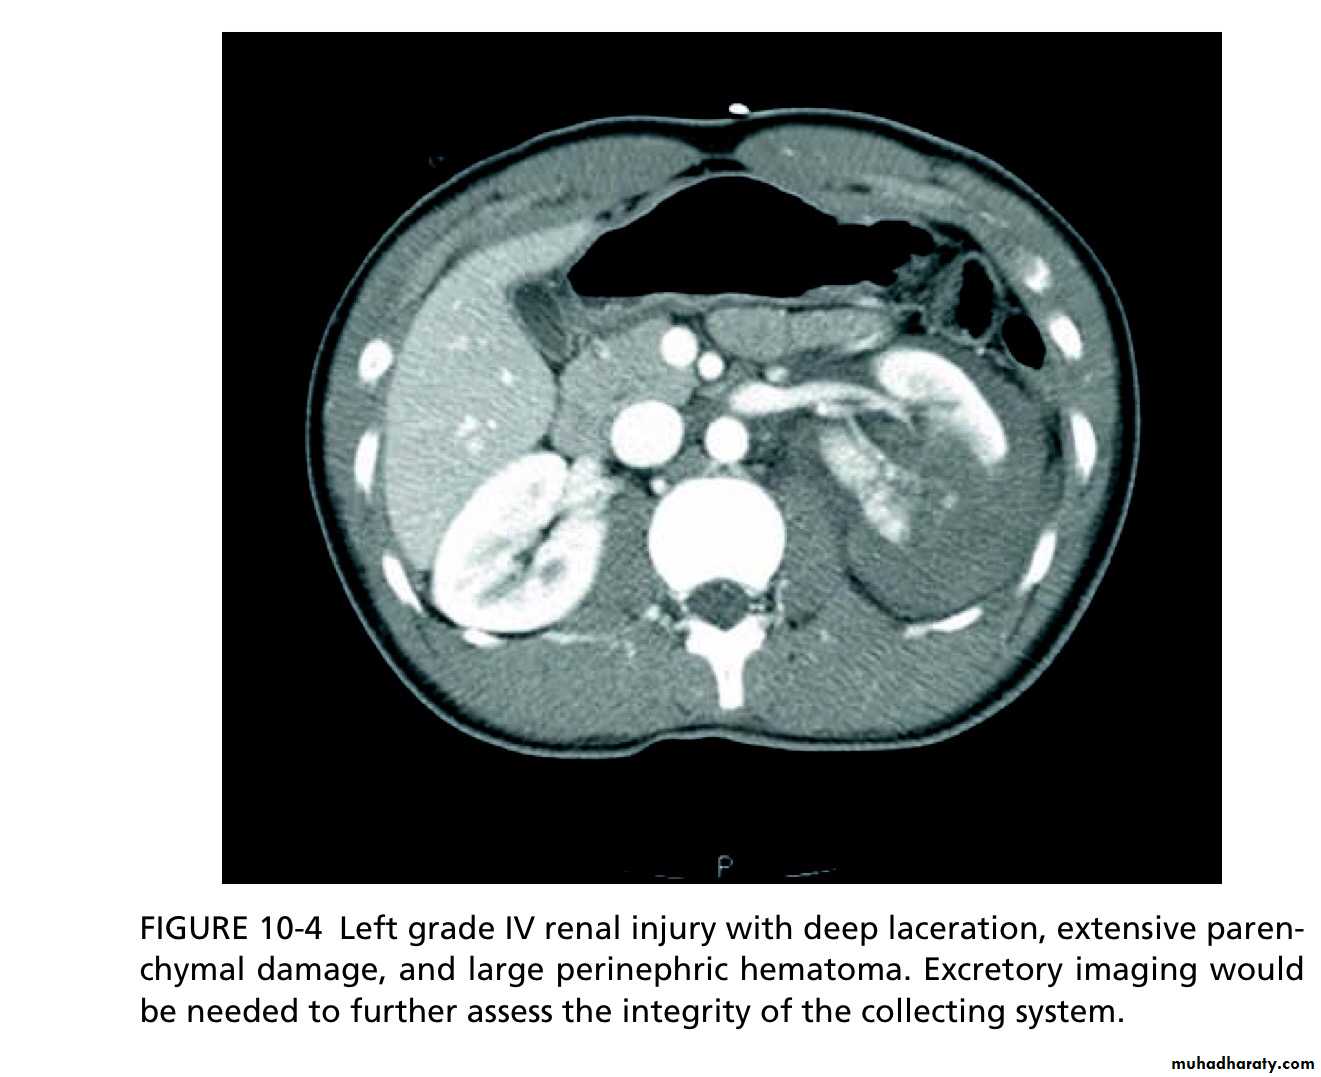

Grade IV

Parenchymal laceration, involving cortex, medulla and collect- ing system OR renal artery or renal vein injury with contained haemorrhage.

High-grade (IV and V) injuries: can be managed non-operatively if they are cardiovascularly stable. However, grade IV and, especially, grade V injuries often require nephrectomy to control bleeding (grade V injuries function poorly if repaired).